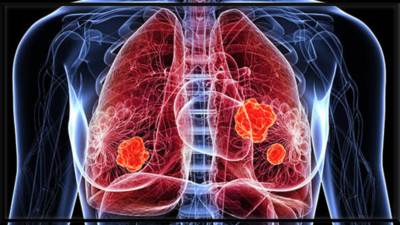

फेफड़े का कैंसर विश्व स्तर पर सबसे आक्रामक कैंसर में से एक है, आमतौर पर इसके उन्नत चरणों में निदान किया जाता है जब इसका इलाज करना कठिन हो जाता है। देरी के लिए एक प्रमुख व्याख्या यह है कि शुरुआती संकेत नरम, गैर-विशिष्ट और आसानी से मामूली बीमारी या जीवन शैली कारकों के साथ भ्रमित होते हैं। निम्नलिखित फेफड़े के कैंसर के छह शुरुआती चेतावनी संकेत हैं जो आमतौर पर व्यक्तियों को अनदेखा करते हैं-एक प्रारंभिक चरण में इसकी मान्यता एक जीवन-रक्षक अंतर बनाती है।

यदि आप सामान्य से अधिक बार सर्दी, ब्रोंकाइटिस, या निमोनिया को पकड़ते हुए प्रतीत होते हैं, खासकर यदि वे एक ही फेफड़े में आवर्ती रहते हैं या पूरी तरह से दूर नहीं जाते हैं, तो यह एक लाल झंडा हो सकता है। एक ट्यूमर वायुमार्ग को अवरुद्ध कर सकता है और फेफड़े को संक्रमण के लिए अधिक असुरक्षित बना सकता है।इनमें से कई लक्षणों को कम गंभीर परिस्थितियों से जोड़ा जा सकता है। लेकिन अगर वे हफ्तों तक जारी रहते हैं या उत्तरोत्तर बिगड़ते हैं, खासकर यदि आप धूम्रपान करने वाले हैं या फेफड़ों की समस्याओं का इतिहास है, तो डॉक्टर से परामर्श करना महत्वपूर्ण है। फेफड़ों के कैंसर का प्रारंभिक पता लगाने से जीवित रहने की संभावनाओं में काफी सुधार हो सकता है और उपचार के विकल्पों का विस्तार हो सकता है।नियमित चेक-अप, शारीरिक परिवर्तन के लिए सतर्क रहना, और धूम्रपान छोड़ना इस मूक हत्यारे के खिलाफ सबसे अच्छा बचाव है